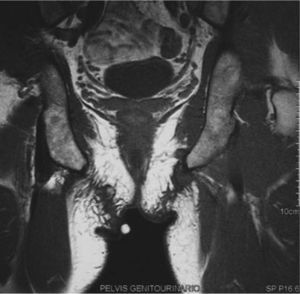

Presentamos el caso de un varón de 49 años, sin antecedentes de interés, que consultó por una lesión dolorosa a la compresión apreciada desde hacía un año sobre la región isquiática derecha. En la exploración física se objetivaba un nódulo de 4 cm, de consistencia elástica, recubierto por piel de características normales. Se solicitó una ecografía y una punción-aspiración que no fueron concluyentes. La resonancia magnética nuclear (RMN) (fig. 1) demostró una lesión nodular de aspecto fibrótico, de 3 cm de diámetro mayor, en íntimo contacto con la cara inferior de la rama isquiática derecha, así como cambios de trabeculación e infiltración de la grasa circundante, compatible con una «induración perineal de los ciclistas». En la región contralateral se observaban cambios similares, aunque menos evidentes. El paciente fue reinterrogado y confirmó su afición al ciclismo.

Clínicamente la induración perineal de los ciclistas suele manifestarse como dos nódulos, uno a cada lado del rafe, aunque ocasionalmente se presenta como uno único («tercer testículo») que se localiza inmediatamente posterior al escroto, cerca de la tuberosidad isquiática. La piel que lo recubre presenta una apariencia normal y su tamaño suele oscilar entre 2-3 cm. A la palpación muestra una consistencia fibro-elástica, pudiendo evidenciarse adherencias al tejido conectivo adyacente1,2. Nuestro paciente consultó por un nódulo localizado en la región isquiática derecha, aunque la RMN reveló también una lesión incipiente de características similares en el lado contralateral.